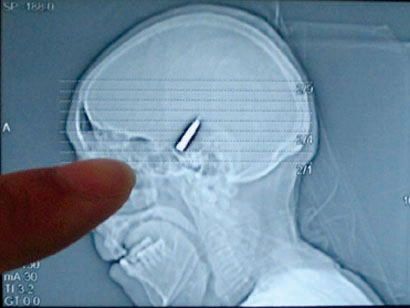

Woman had bullet in head for 64 years

A Chinese grandmother who went to hospital with a headache was found to have had a bullet in her head for 64 years.

Jin Guangying, 77, of Shuyang town, Jiangsu province, went to to Shuyang Leniency Hospital for an x-ray.

“We were surprised to learn there was a bullet inside her head,” her son, Wang Zhengbang, told the Yangtse Evening Post.

Jin remembers that she was shot in 1943 during the Second World War by the invading Japanese army when she was taking supplies to her guerrilla father.